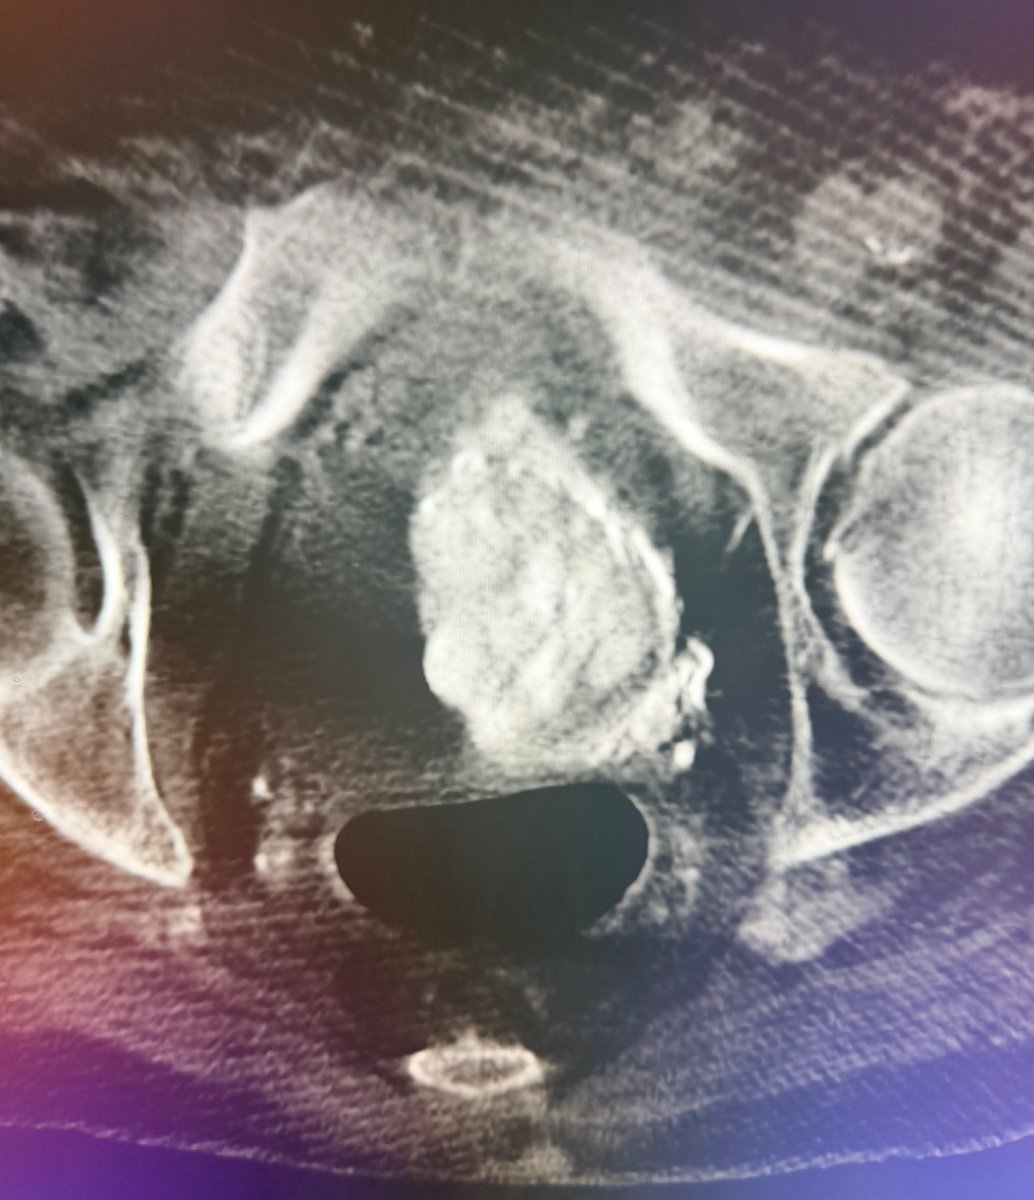

A patient with IVC atresia rolled into my office in a wheelchair. No options were offered for years. Successful IVC reconstruction. One week later, walked into my office for followup! One month later, living his best life, no pain and no limitations. #chogazi #irad #vascular #cardiotwitter @SIRRFS @SIR_ECS @SIRspecialists @VascularSVS @farkomd @AmputationSuck @ChengaziMD